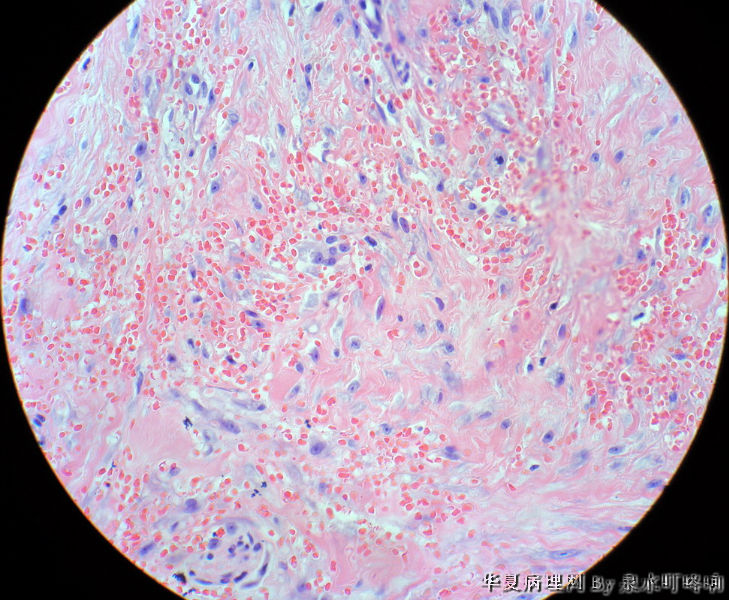

男,49岁,左肩胛部肿物。

图2